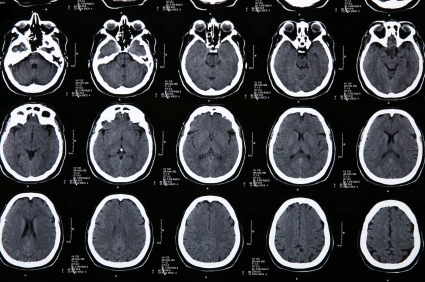

Кроме типичной клинической картины различных вариантов нейросифилиса ведущим методом диагностики является серологический (реакция Вассермана, микрореакция преципитации с кардиолипиновым антигеном, реакция иммунофлюоресценции - РИФ, реакция иммобилизации трепонем - РИТ), КТ и МРТ головного мозга при нейросифилисе выявляют изменения и служат для исключения других заболеваний.

Медицинские процедуры, проводимые при заболевании нейросифилис: Биохимический анализ крови, Клинический анализ крови, Спиральная компьютерная томография, Магнитно-резонансная томография, Реакция Вассермана, Реакция иммунофлюоресценции (РИФ), Реакция иммобилизации бледных трепонем (РИБТ), Компьютерная томография